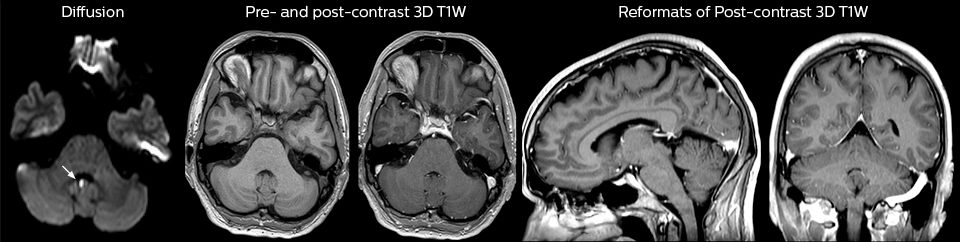

A range of protocol sheets was developed to help ensure that referring physicians order the most appropriate MRI exam. The optimized MRI protocols also include 3D contrast-enhanced imaging, allowing neurosurgeons to comfortably use the isotropic data in the operating room while performing stereotaxic surgery.